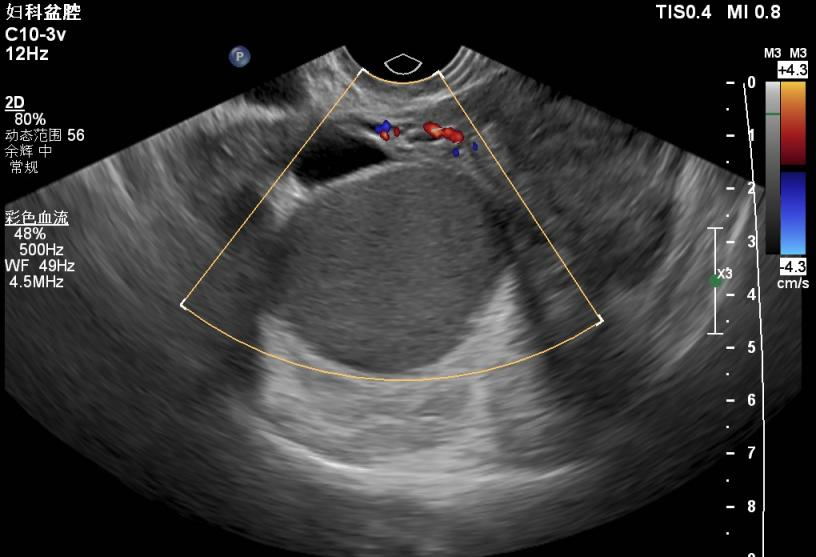

患者张xx,女,29岁。就诊时间:2021年3月20日。 主诉:继发性痛经伴进行性加重2+年。 现病史:患者自2018年10月份开始无明显诱因出现月经期下腹痛,起初未在意,未就诊。现因痛经进行性加重,NRS疼痛评分5分,伴性交痛,为进一步诊治就诊。 既往史:既往体健,无特殊既往史可询。 个人史:无特殊个人史可询。 月经史:14岁初潮,5/28天,经量中等,2018年开始出现痛经。 婚育史:22岁结婚,孕2产1,2015年足月顺产分娩1女,2017年自然流产1次。 家族史:无特殊家族史可询。 妇科检查:外阴已产式,阴道畅,宫颈光滑,大小正常,质中,子宫后位,宫体大小正常,形态规则,活动欠佳,后穹隆可及触痛结节,右侧附件区可扪及一个大小约7cm*6cm*5cm的囊性肿物,活动欠佳,伴触痛,左侧附件区未扪及明显异常。 辅助检查: B超:子宫后位,宫体大小正常,宫腔线居中,内膜厚4mm,肌层无明显增厚,右侧附件区可见大小约76mm*58mm*54mm的囊性肿物,内可见密集细弱光点,左侧附件区未见显异常回声。 术前B超:右侧卵巢囊肿 诊断: 诊断依据: 处理:患者继发性痛经伴进行性加重,B超检查提示卵巢子宫内膜异位囊肿>4cm,患者近期内有生育要求,予以行腹腔镜下卵巢子宫内膜异位囊肿剥除术+盆腔子宫内膜异位病灶切除术,术后予以地屈孕酮口服减少内异症复发并随访。 1.诊疗思路: (1)长期管理,坚持以临床问题为导向,以患者为中心,分年龄阶段处理,综合治疗; (2)基于临床诊断尽早开始经验性药物治疗; (3)规范手术时机,注意保护卵巢功能和生育力,使患者的手术获益最大化; (4)保守性手术后进行药物长期管理,综合治疗,预防复发; (5)内异症患者应定期复查,对有恶变高危因素的患者应警惕恶变。 患者继发性痛经伴进行性加重,B超检查提示卵巢子宫内膜异位囊肿>4cm,根据中国子宫内膜异位症诊治指南(第三版),有手术指征,针对该患者的病情,我们采取了腹腔镜手术+术后药物长期管理的治疗策略,并鼓励患者恢复后尽早备孕。 2.手术治疗: 术后病理: (1)右侧卵巢子宫内膜异位囊肿; (2)(盆腔病灶)可见含铁血黄素陈旧,考虑为子宫内膜异位; (3)患者术后恢复良好,于2021年3月26日出院。 3.术后长期管理: 4.术后随访: 妇科检查:阴道后穹隆触痛结节不明显,双侧附件区未扪及明显异常。复查盆腔彩超未提示巧囊复发。嘱患者继续规律服药。 第一次复查 ②2021-12-06,患者第二次随访。痛经情况较术前明显缓解,NRS疼痛评分1分。患者期间一直遵医嘱规律服用地屈孕酮,月经正常。 妇科检查:阴道后穹隆未扪及触痛结节,双侧附件区未扪及明显异常。复查盆腔彩超未提示巧囊复发。嘱患者继续规律服药。 第二次复查 ③2022-04-17,患者第三次随访。患者自术后已规律服用地屈孕酮1年,月经正常,痛经已完全缓解,无性交痛,NRS疼痛评分0分。 妇科检查:阴道后穹隆未扪及触痛结节,双侧附件区未扪及明显异常。复查盆腔彩超未提示巧囊复发。建议患者可继续规律服用地屈孕酮。 第三次复查 子宫内膜异位症是生育期女性的常见病,多发病,约10%的生育期女性患有内异症。其主要症状是下腹痛和痛经,还可表现为慢性盆腔痛和性交痛,除此之外还有不孕、月经异常等表现。内异症可影响生殖系统各个部分,导致卵巢功能受损,生育力下降。2021年中国子宫内膜异位症诊治指南(第三版)指出内异症治疗应以患者为中心,分年龄阶段处理,规范手术时机,在保守性手术后应予以长期药物管理及定期复查[1]。 内异症的药物治疗主要分为非甾体类抗炎药(NSAID)、孕激素类、复方口服避孕药(COC)、促性腺激素释放激素激动剂(GnRH-a)及中药等。其中孕激素又包括地屈孕酮和高效孕激素,如地诺孕素、甲羟孕酮、左炔诺孕酮宫内释放系统(LNG-IUS)[2-3]。 地屈孕酮的优势在于控制内异症的同时不抑制排卵,适合有生育需求的患者[4]。全周期口服地屈孕酮片10-20mg/d,可有效控制内异症,同时可改善孕激素抵抗,增加妊娠机会[5]。 本病例中患者有明确的近期内生育要求,故不适宜予以GnRH-a、COC、地诺孕素等药物;同时患者EFI评分7分,患者拒绝试管婴儿等辅助生殖技术。因此,我们在与患者及家属沟通后给予患者月经第5-25天,地屈孕酮10mg/d,口服来减少内异症的复发并在服药前给患者做了乳腺彩超排除了乳腺结节。患者服药3个月即感到痛经明显缓解,术后规律服药1年后痛经完全消失,起到了良好的治疗效果。地屈孕酮得益于其服药期间不干扰受精卵着床,增强自然受孕能力,对有生育需求的患者具有优势[6]。同时,长期服用地屈孕酮对肝脏影响小,不引起骨质疏松,是内异症长期管理的优选药物之一[7-8]。 参考文献: 赵晨阳 医生 湖南省郴州市第一人民医院(湘南学院第一附属医院) 湖南省郴州市第一人民医院(湘南学院第一附属医院)妇科 副主任医师,医学硕士,毕业于中南大学湘雅医学院 ❖湖南省郴州市妇产科专业委员会秘书 ❖主攻方向:妇科恶性肿瘤规范化治疗和妇科微创手术 ❖目前主持湘南学院校级课题1项,院级课题1项,院内新技术项目1项

3.B超检查提示右侧附件区可见大小约76mm*58mm*54mm的囊性肿物,内可见密集细弱光点。